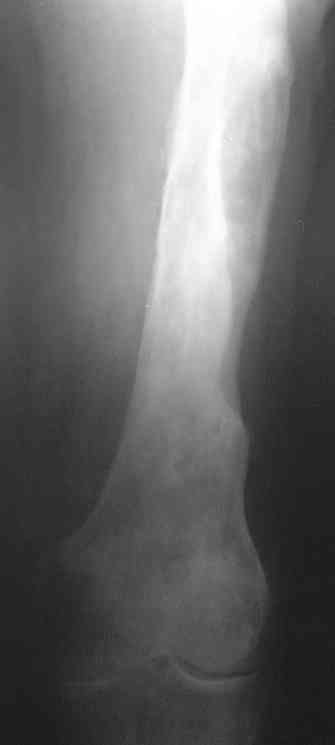

Больной 53 лет, страдает остеомиелитом с 1975г.,после закрытого перелома с/3 бедра и интрамедулярного остеосинтеза. Выполнено более 30 операций без особого эффекта. Какой комплекс операций может помочь больному? Больной, 1954 г.р.Клинический диагноз: хронический травматический тотальный остеомиелит левой бедренной кости, секвестрально - свищевая форма, часторецидивирующее течение. Ложный сустав шейки левой бедренной кости. Укорочение левого бедра 10 см. Контрактура коленного сустава. Жалобы: боли в области левого бедра, коленного сустава, нарушение функции левой ноги, наличие свища с гнойным отделяемым в левой подколенной области, свища в области в\з бедра. Анамнез: в 1975 г. получил закрытый перелом с\з левой бедренной кости. Оперирован в районной больнице - выполнена открытая репозиция, интрамедуллярный остеосинтез. Осложнение - нагноение раны с исходом в остеомиелит бедренной кости. В последующий годы - трижды патологический перелом бедра. Оперирован за эти годы около 30 раз по поводу обострения остеомиелита. За последние 5 лет обострения ежегодно по 2- 3 раза в год. Динамика отрицательная. Рентгенологически - тотальное поражение бедренной кости. Объективно: передвигается при помощи костылей с дозированной нагрузкой на левую ногу. При нагрузке на левую ногу - стопа в положении эквинуса, опора на передний отдел стопы. Выражена атрофия мышц левого бедра, голени. На всем протяжении бедра - множественные рубцы после оперативных вмешательств. В в\з бедра по наружной поверхности - грубый втянутый рубец с вялогранулирующей раной на дне его. Отделяемого нет. В области подколенной ямки - свищ с гнойным отделяемым серо - зелоноватого цвета без запаха. Укорочение бедра 10 см. Движения в тазобедренном суставе активно 180 - 160 град., пассивно 180 - 90 град. В коленном уставе 178 - 110 град. Чувствительных расстройств конечности нет.Лабораторные данные: Общ. ан. крови: 20.04.07. Нв-135 г\л, Er 4.22 млн., Le-9.7 тыс, Эоз. 4%, Пал.-5 %, Сегм.-60 %, Лимф. - 25 %, Моноц.-6 %, СОЭ 51мм\час.Биохимический ан. крови от 20.04.07г. Белок -77 г/л, сахар крови 5.38 ммоль/л., билирубин 10.2 мкмоль/л. Тимоловая проба 2.5 ед.пом. Ан.мочи от 20.04.07. : отн. плотность1026, белок - отр, сахар -отр, ЭКГ от 22.02.07 : отклонение ЭОС влево.. Неполная блокада правой ножки пучка Гиса. Флюорография от 28.12.2006 года № 038 - без патологии. R - графия : грубая деформация и склерозирование бедренной кости от проксимального до дистального метафиза , множество очагов просветления в области дистального метаэпифиза, н\з бедра. МРТ коленного сустава, н\з бедра от 21.04.2007г. - картина хронического остемиелита левой бедренной кости. Имеется полость деструкции в дистальном метадиафизе протяженностью до 12 см. Полость имеет неоднородное содержимое за счет гноя, грануляций, секвестров, сообщается со свищевым ходом, идущим в подколенную ямку.